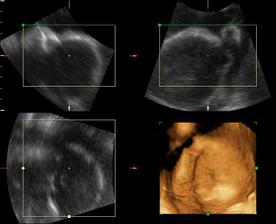

Od 19. júna 2008, teda od 21. týždňa vieme, že sa nám na 99% narodí dievčatko...na mene neodznela ešte úplná zhoda, preto Ema alebo Silvia...no ja dúfam, že sa mi podarí presadiť Emu, aj keď Silvia je tiež krásne meno...🙂...

a dnes, 16.10.2008, teda v 38. týždni, padlo definitívne rozhodnutie o mene...skôr moje rozhodnutie ako tatkove...🙂...takže naša prvorodená dcérka sa bude volať Ema Silvia...🙂